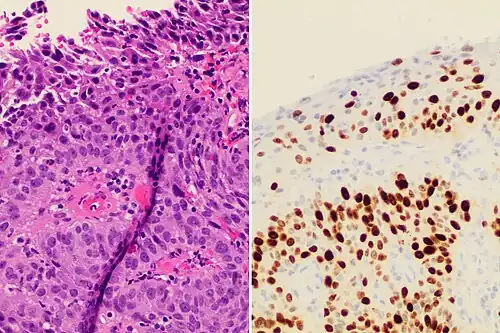

Invasive squamous cell carcinoma of the cervix is characterized by infiltration as irregular anastomosing nests or single cells.[75] This case is poorly differentiated. H&E stain. -

Cervical squamous cell carcinoma generally shows diffuse staining of both nuclei and cytoplasm on p16 immuno-

histochemistry (except verrucous variant).[76] -

Invasive cervical squamous cell carcinoma on H&E histopathology and Ki-67 immunohistochemistry. The latter correlates well with the degree and level of dysplasia.[77] -